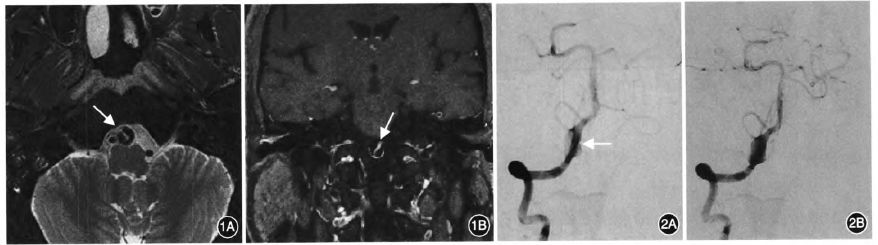

我们来看看夹层的影像特征就知道二者的密切关系,动脉夹层病变相关的典型影像学征象包括:(1)动脉偏心性狭窄伴外管径扩张。(2)串珠征或节段性狭窄。(3)壁内血肿。(4)双腔征。(5)内膜瓣。(6)夹层动脉瘤形成。

双腔征